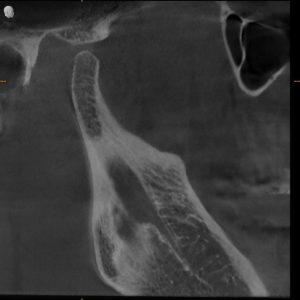

MRI Findings:

- Bilateral disc displacement without reduction

- This explained everything — the pain, the restriction, the dysfunction